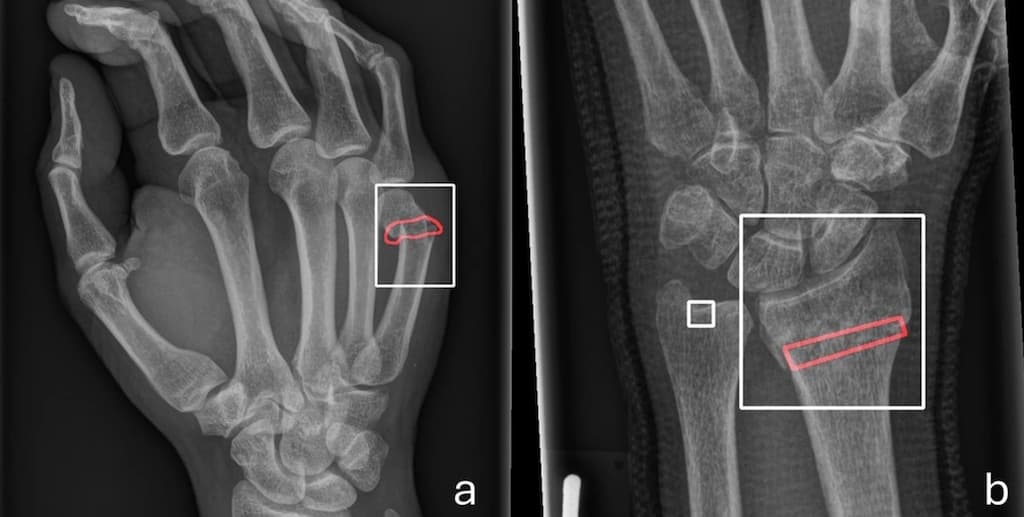

Une IA dédiée pour identifier les fractures en radiologie pédiatrique

En traumatologie pédiatrique, les solutions d’IA ne pas toujours pertinentes pour assister les praticiens qui cherchent à identifier une anomalie musculo-squelettique. Des chercheurs allemands ont publié un article dans la Revue European Radiology dans lequel ils évaluent les performances d’un algor...

Une IA entraînée sur des cohortes hétérogènes est plus performante pour identifier les fracture en radiographie

Pour améliorer le diagnostic de fracture en radiographie conventionnelle assisté par l’IA, celle-ci doit être entrainée sur des cohortes hétérogènes. Une étude publiée dans la Revue European Radiology évalue un outil d’IA conçu en inde pour l’aide à l’interprétation de patients néerlandais. Les cher...